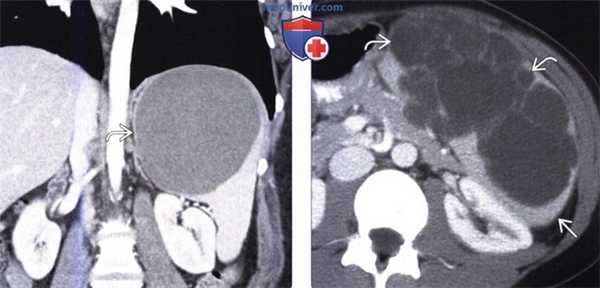

(Справа) Макропрепарат удаленной (у этого же пациента) селезенки: кальцинированная стенка кисты, состоящая из фиброзной ткани. Эта киста является приобретенной и возникла, скорее всего, в результате травмы или инфаркта. (Слева) На корональной КТ с контрастным усилением у молодой девушки визуализируется большая киста в селезенке, выглядящая простой. Пациентка предъявляла жалобы на боль и раннее насыщение, ей было выполнена операция — иссечение стенки кисты.

(Справа) На аксиальной КТ с контрастным усилением определяется большая киста, с множественными перегородками в структуре, не накапливающая контраст, занимающая большую часть объема селезенки, и только лишь небольшой участок ее паренхимы в задних отделах остается интактным.

(Слева) На корональной КТ с контрастным усилением у молодой девушки визуализируется большая киста в селезенке, выглядящая простой. Пациентка предъявляла жалобы на боль и раннее насыщение, ей было выполнена операция — иссечение стенки кисты.